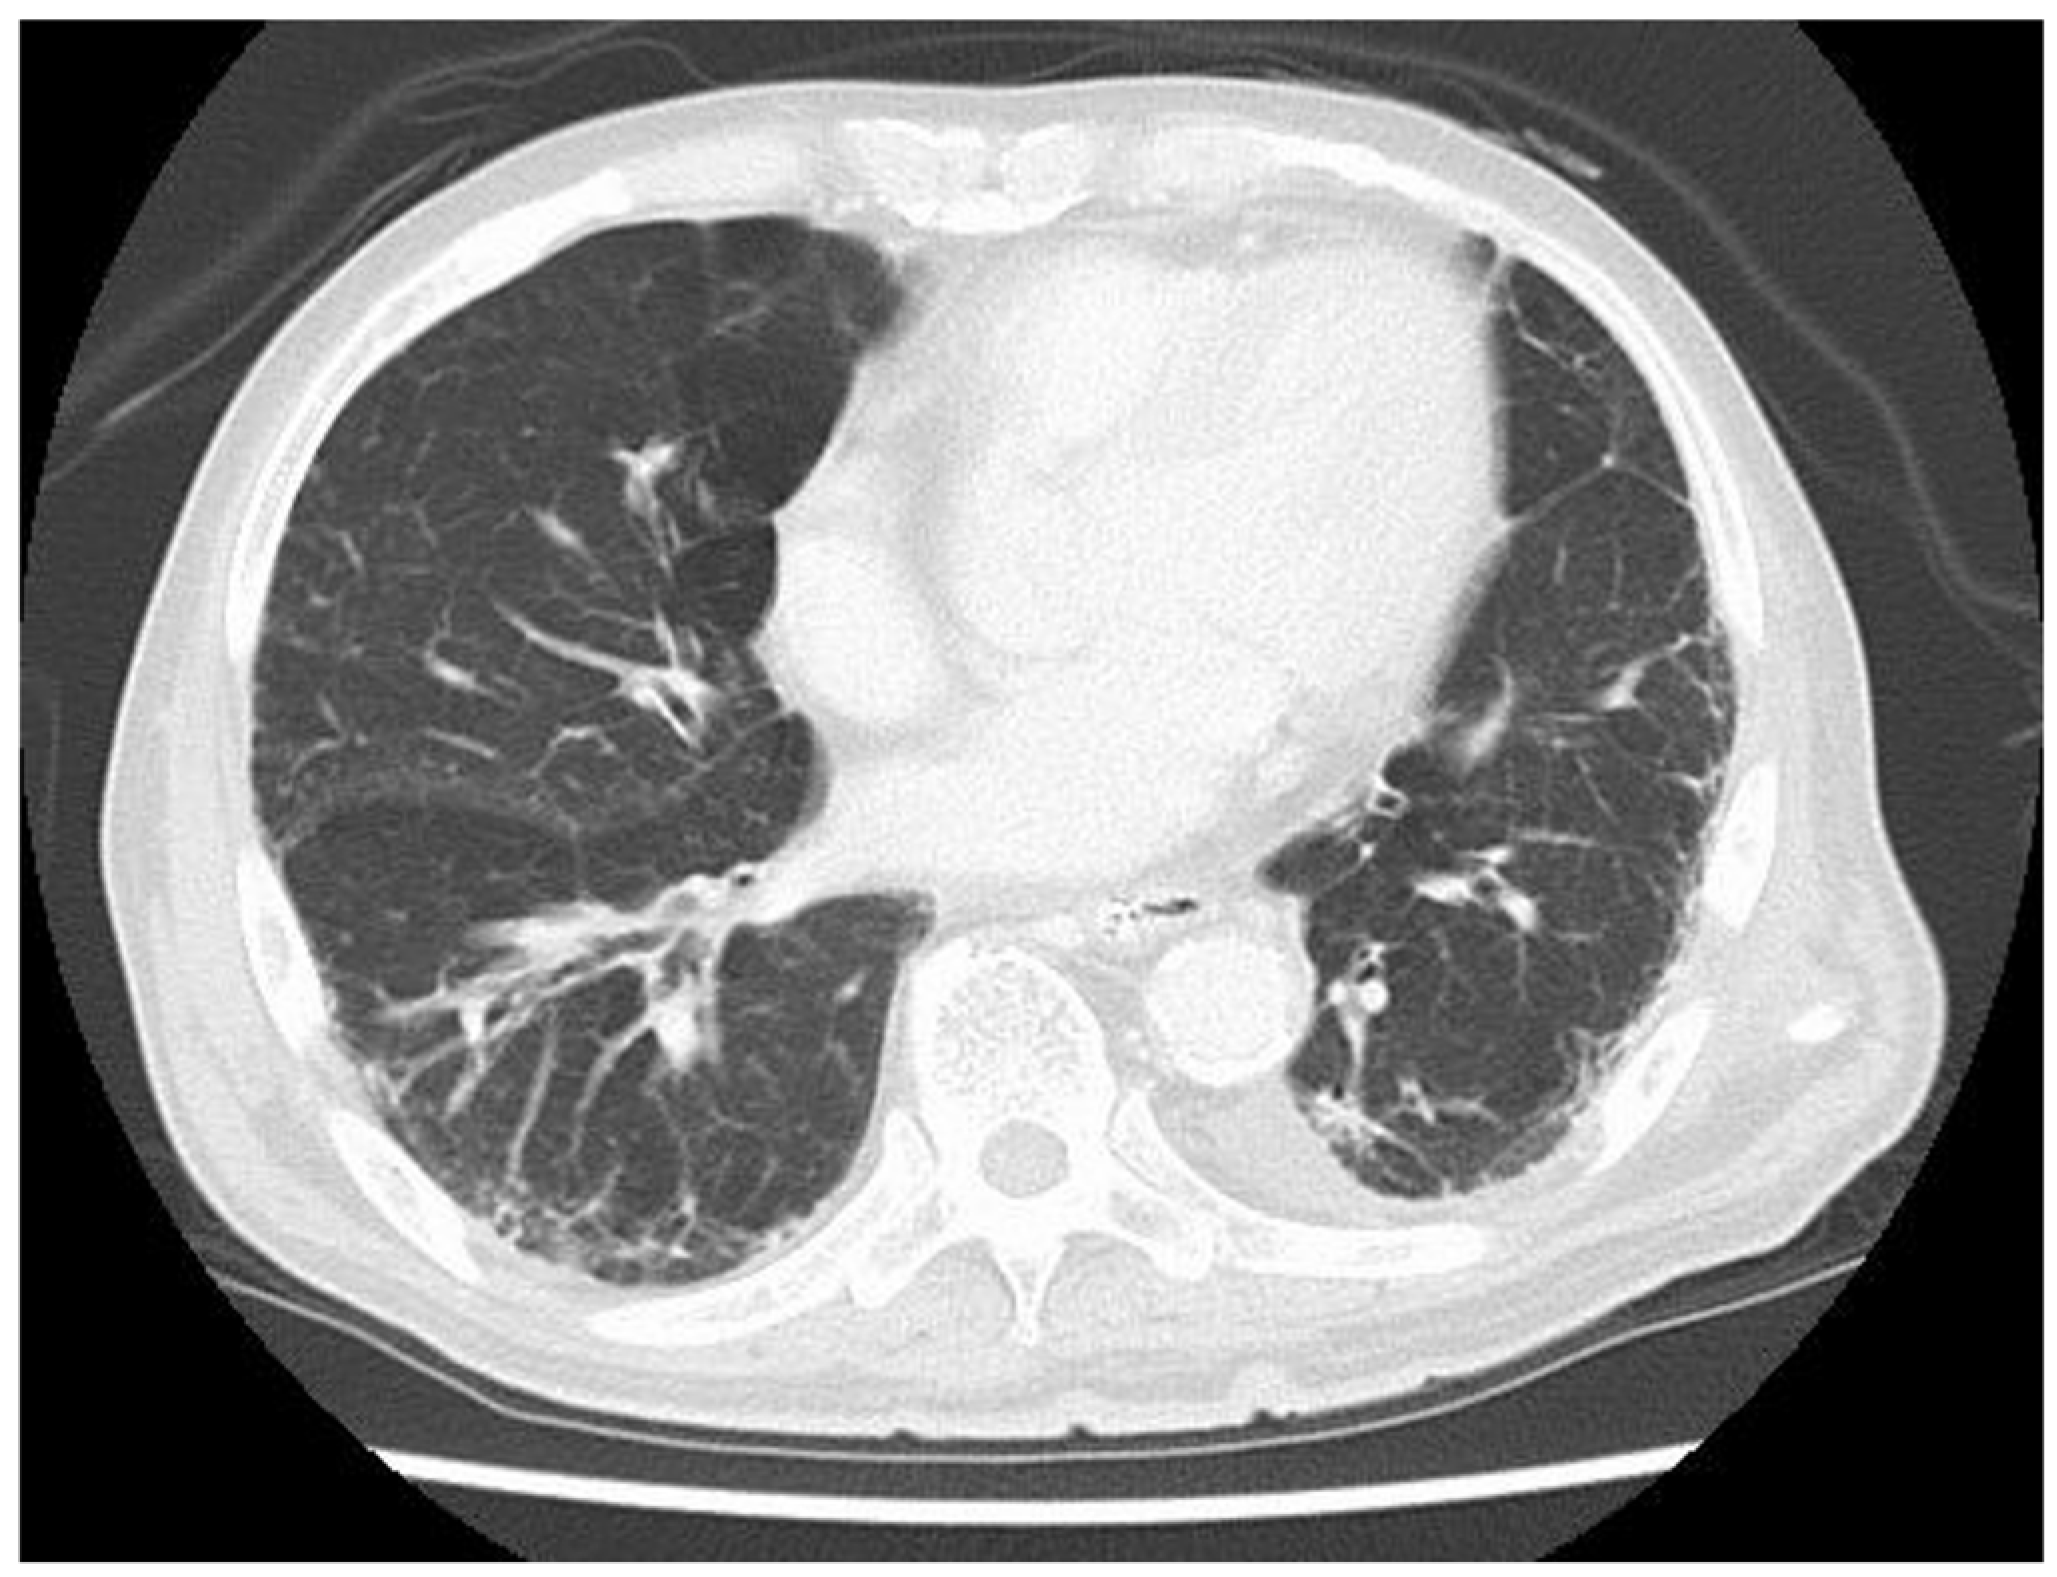

2. Case Presentation